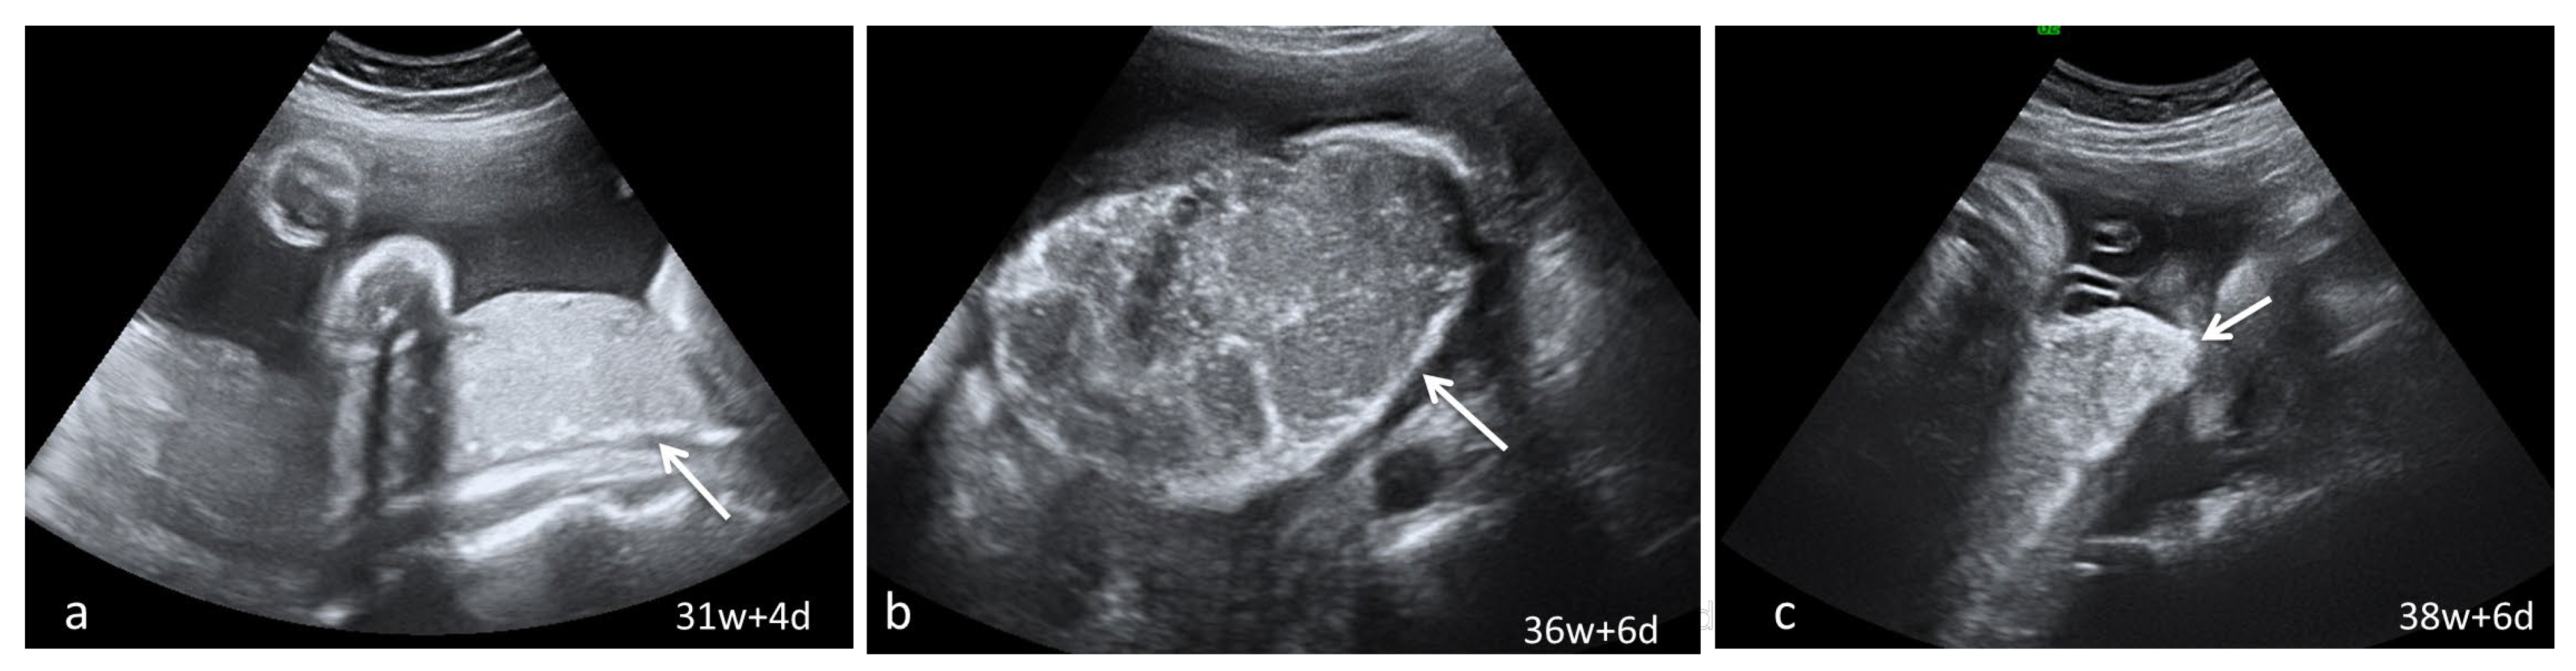

Dynamic evaluation of the placental morphology revealed what seems to be a particular pattern of placental remodeling starting from 30 WG towards term following SARS-CoV-2 infection during pregnancy. We noted the occurrence of dispersed hyperechoic foci, without posterior acoustic shadowing, scattered across the placenta, increasing in number and size with consecutive examinations, creating a “starry sky” appearance similar to the sonographic pattern described in acute hepatitis (Figure 1) [22]. Consequently, these foci conflate to form interlobular, chandelier-like, comma-shaped indentations. Later, lesions organize to form a consistent, chalky conglomerate along the entire basal plate, a “white line”, with bolded edges towards the chorionic plate forming white angles (Figure 2). Placental changes mimic the physiologic aging process but occur earlier in gestation; echo-dense foci are more widespread and organize in a short period to form the echoic white line.

Serial placental ultrasound images at 31 WG, 36 WG and 38 WG, respectively, of a nullipara with confirmed SARS-CoV-2 infection at 24 WG (a) the “white line” (arrow) beginning to form at the level of the basal plate; (b,c) continuous “white line” with bolded angles towards placental margins.